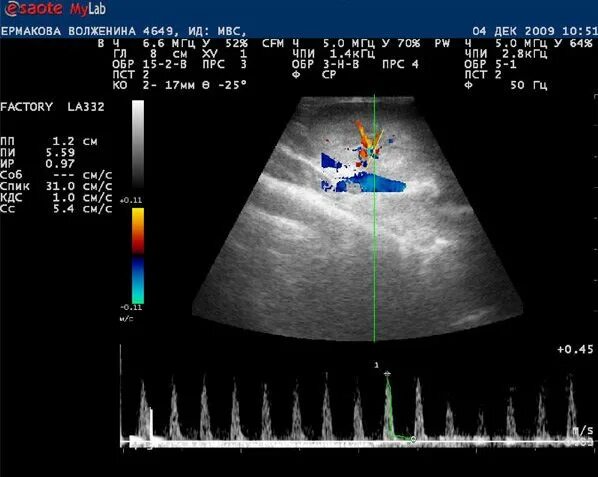

Нефросклероз почек на узи что это такое